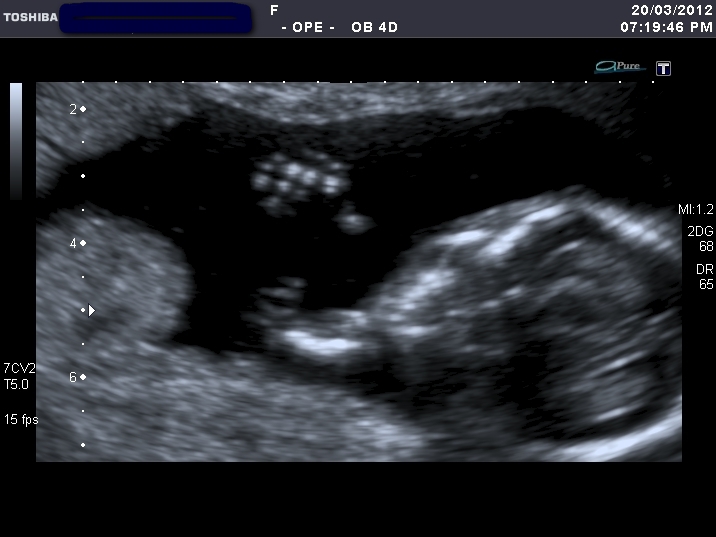

I'm clueless what these represent, perhaps one is potty shot? If so, enlighten me where to look!lol

Attachment 1798 Attachment 1799Attachment 1800 Attachment 1801